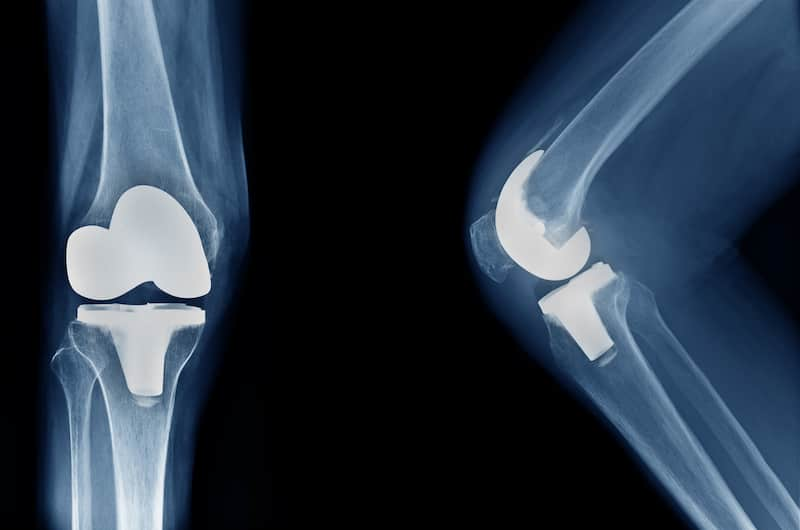

Joint Replacement Surgery

These pages are designed to give you the right information about some common joint replacement surgeries, along with some advice and exercises to help you with your rehabilitation.